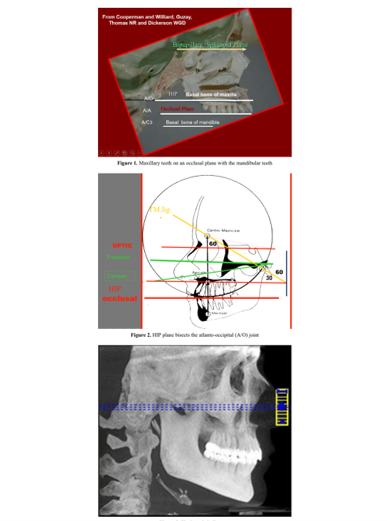

Hội thảo thuyết trình về Khớp cắn trong Nha Khoa Kính mời quý đồng nghiệp tham gia buổi thuyết trình về đề tài Khớp cắn trong Nha Khoa Kỹ Thuật Số Trình bày bởi Dr Kerstein Tufts Medical and Dental University USA tại giảng đường A,B Lúc 8g ngày 02/4/ 2019. Lớp DTR về điều trị loạn […]